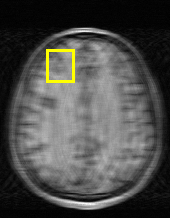

Edge preserving has always been a crucial concern in the design of reconstruction models. To improve the quality of reconstructed images and preserve image edges, some works suggested introducing edge priors in the original restoration problem to preserve image edges [4, 34]. However, they will suffer from complicated algorithm design and time-consuming training processes. Recently, some more efficient methods have been proposed to use edge maps as external guidance for image restoration. For example, Yang et al. [48] used off-the-shelf edge detectors to extract image edges from the degraded images. Fang et al. [12] predicted image edges by constructing an edge reconstruction network. Huang et al. [18] designed a novel dual discriminator GAN framework for solving fast multi-channel MRI, in which one GAN network is built for edge information enhancement. Inspired by these methods, we also consider introducing image edge prior as external guidance to MRI reconstruction since 1) image edges are prominent and distinguishable features in MRI (see Fig. 1), which can serve as a good guide to the model to recover high-frequency details; 2) the ground truth edges can be easily fetched via ordinary edge extraction operators, like Canny, Sobel, and Prewitt, which means that the edge maps can be learned in a data-driven manner. However, how to effectively utilize image edge priors to guide image reconstruction still remains a challenge. In some methods, edge information was simply concatenated with the input image and passed to the next stages. Though this is a simple way to utilize the edge priors, it may not give full play to the guiding role of the edge priors. Therefore, in this work, we want to explore a more efficient and effective mechanism to fully take advantage of image edge priors.

(a)

(b)

(c)

fastMRI is a large-scale MR dataset jointly established by Facebook AI Research and NYU Langone Health. It provides both knee and brain datasets for evaluation. In our work, we use the multi-coil knee dataset, which was acquired on three clinical 3T systems or one clinical 1.5T system using a 15-channel knee coil array. The dataset includes data from two pulse sequences, yielding coronal proton-density weighting with (PDFS) and without (PD) fat suppression. As is shown in Fig. 1, PD images usually contain more structural and prominent edge features than PDFS images, which suggests that it is more challenging to use edge guidance on PDFS datasets. Therefore, we explore the effectiveness of EAMRI on these two modalities. Following [13], for both PD and PDFS knee datasets, we separately filter out 227 volumes (8332 slices) for training and 24 volumes (1665 slices) for testing. The dataset is centrally cropped to .